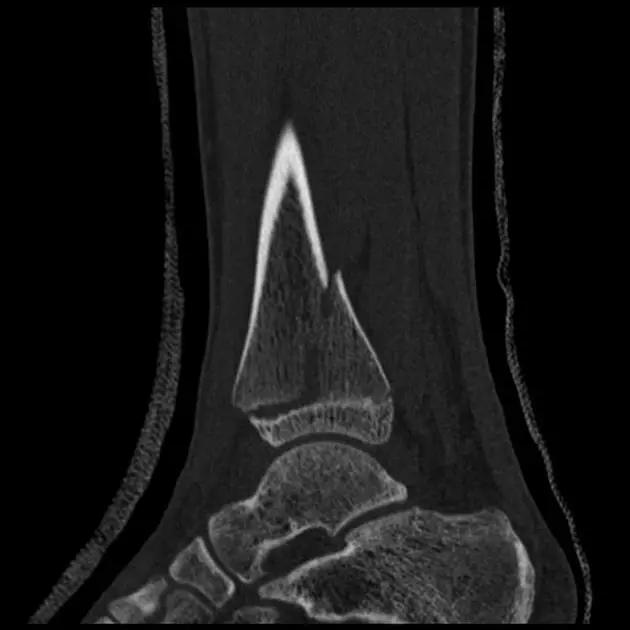

6. Pilon 骨折

涉及负重关节面(胫距关节面)与胫骨远侧干骺端的骨折。其典型特征是干骺端存在不同程度的压缩、干骺端的压缩粉碎性骨折不稳定、原发性关节软骨损伤以及永久性关节面不平整导致预后不良。

pilon 骨折正位片

pilon 骨折侧位片

pilon 骨折三维 CT 表现